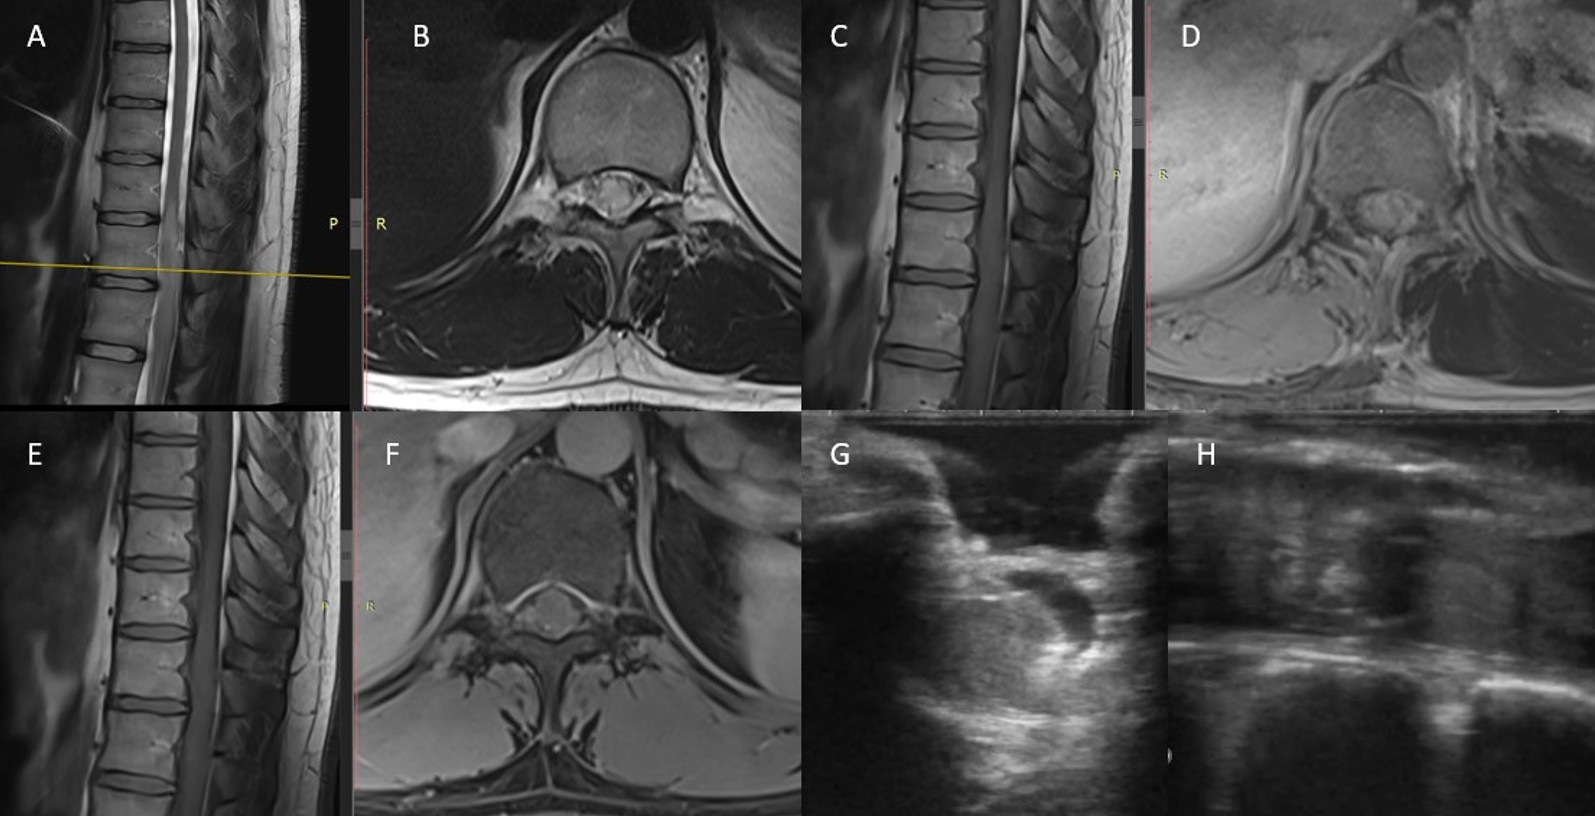

H3K27M mutasyonu taşıyan diffüz orta hat gliomları (DMG), yakın zamanda WHO grade IV olarak sınıflandırılan nadir ve agresif santral sinir sistemi tümörleridir. Çoğunlukla pediatrik beyin sapı gliomlarında görülmekle birlikte, yetişkinlerde omurilik tutulumu seyrektir ve özgün tanısal ve terapötik zorluklar içerir. Bu yazıda, giderek artan sırt ağrısı ve T12 dermatomu altında duyu bozukluğu ile başvuran 27 yaşındaki erkek hasta sunulmaktadır. Manyetik rezonans görüntüleme (MRG), T10–T12 seviyelerinde genişleyici intramedüller bir lezyon ortaya koymuştur. Cerrahi müdahale ile total rezeksiyon sağlanmış ve histopatolojik inceleme H3K27M pozitifliği, yüksek Ki-67 proliferasyon indeksi ve belirgin p53 ekspresyonu ile uyumlu DMG tanısını doğrulamıştır. Postoperatif dönemde hasta 54 Gy radyoterapi almış ve temozolomid tedavisine başlanmıştır. Beş aylık takipte tekrarlama izlenmemiştir. H3K27M mutasyonuna sahip omurilik DMG’leri biyolojik olarak agresif seyirli olup genellikle genç erişkinlerde görülür. Yüksek proliferatif aktivite göstermeleri ve MGMT promotör metilasyonunun olmaması, temozolomid gibi alkilleyici ajanlara sınırlı yanıtla ilişkilidir. Total rezeksiyon tek başına kür sağlayamasa da multimodal tedavi kısa süreli hastalık kontrolü sunabilir. Bu tümörlerin yönetiminde ilerleme kaydedebilmek için hedeflenmiş epigenetik tedavilere yönelik araştırmaların sürdürülmesi kritik öneme sahiptir.